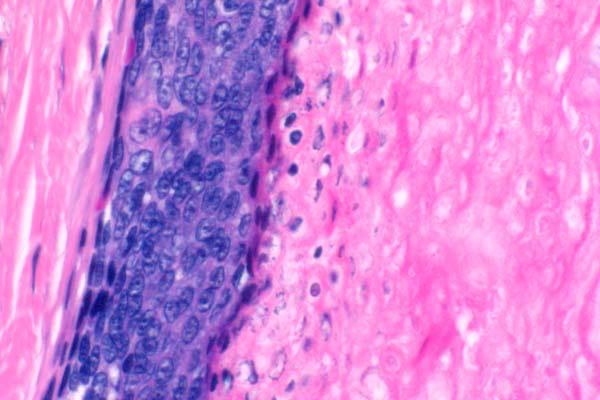

Abrupt keratinization is characterized by a sharp delineation between neoplastic cells and keratinaceous material. There are ghost cells in the keratin (arrowheads).